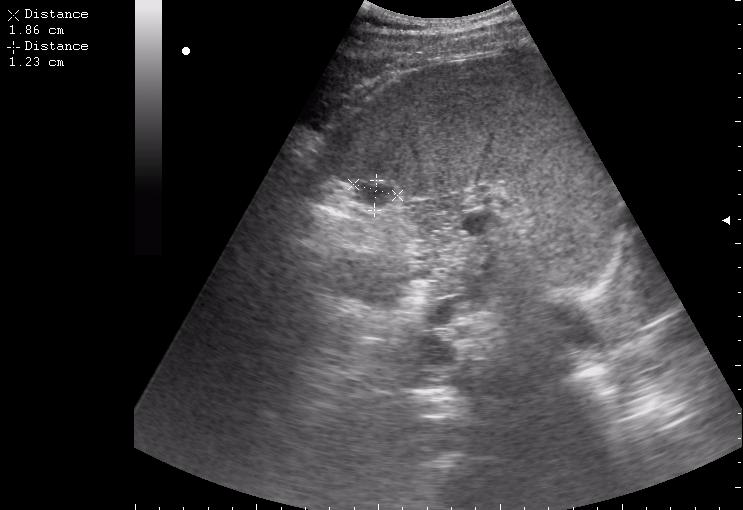

железный дрын вошел в правую подвздошную область, остановился в капсуле печени.

мальчик лежал на спине (переломы костей таза). на затёки крови не похоже.